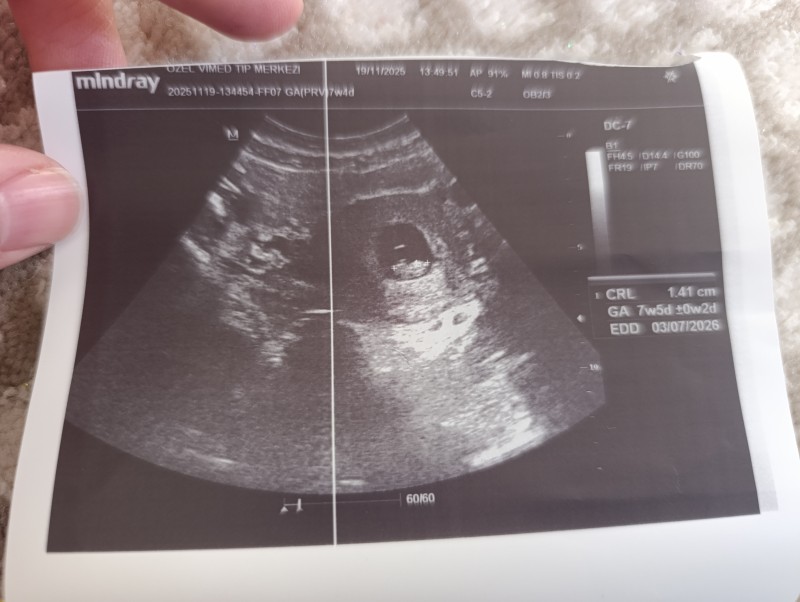

Kızlar cinsiyet tahmini yapabilir misiniz.? Eğlencesine soruyorum

Bu arada 7+5 haftalık . Yazmayı unutmuşum

Kız gıbı canm Rabbim gönlüme göre versin bırde kese de ultrason görüntüsüne göre sagda çıkmış kız bence  😊